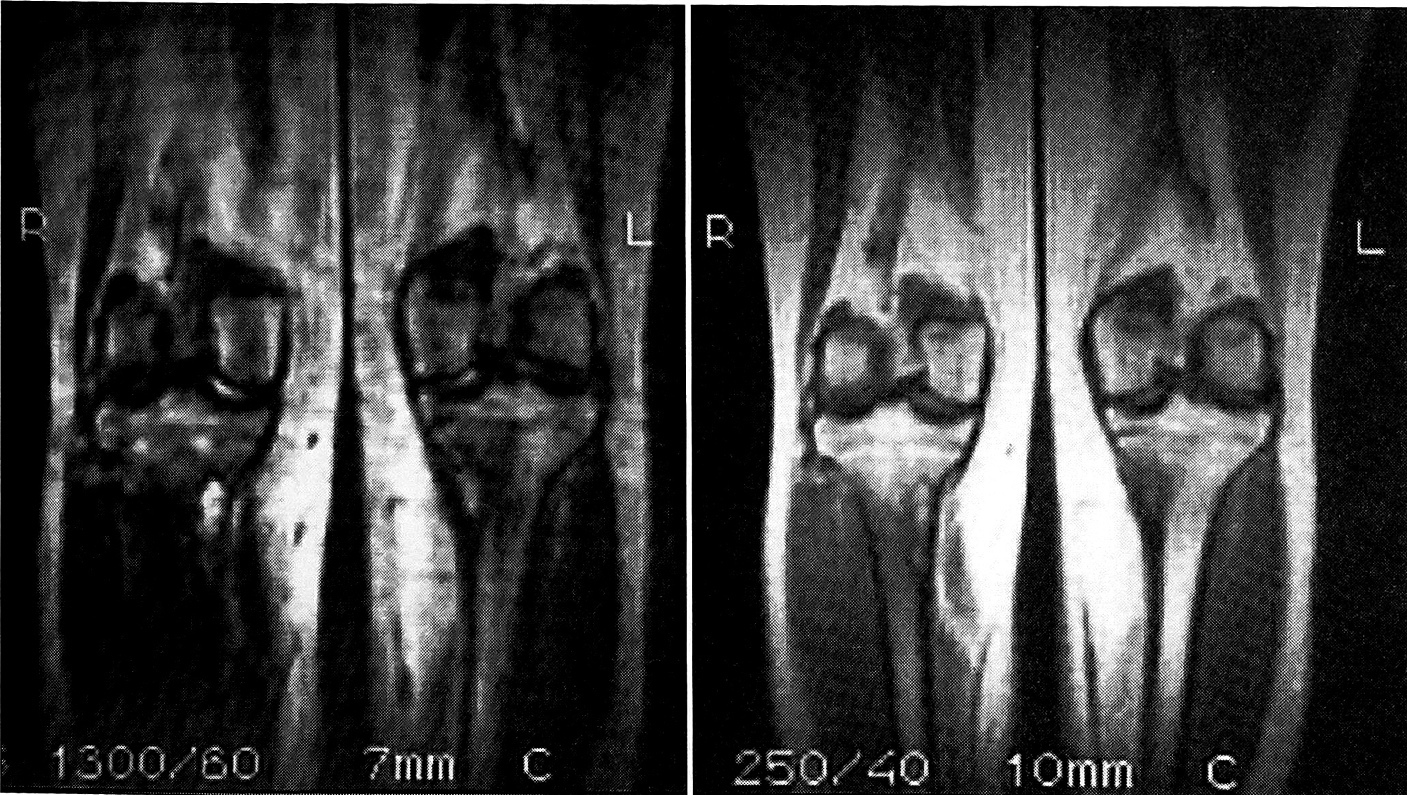

МРТ была применена у одной пациентки с целью дифференциальной диагностики. На серии магнитно-резонансных томограмм в области проксимальных метафизов длинных костей определялись участки неправильной формы с повышенной интенсивностью сигнала на Т2 взвешенных изображениях. На Т1 взвешенных изображениях регистрировался изоинтенсивный сигнал. Изменения интенсивности сигнала с мягких тканей в области исследования не выявлено. МРТ позволила полностью исключить поражение мягких тканей в проекции патологических очагов (рис. 4).

Рис. 4. Магнитно-резонансные томограммы больной М. с синдромом Jaffe— Campanacci.